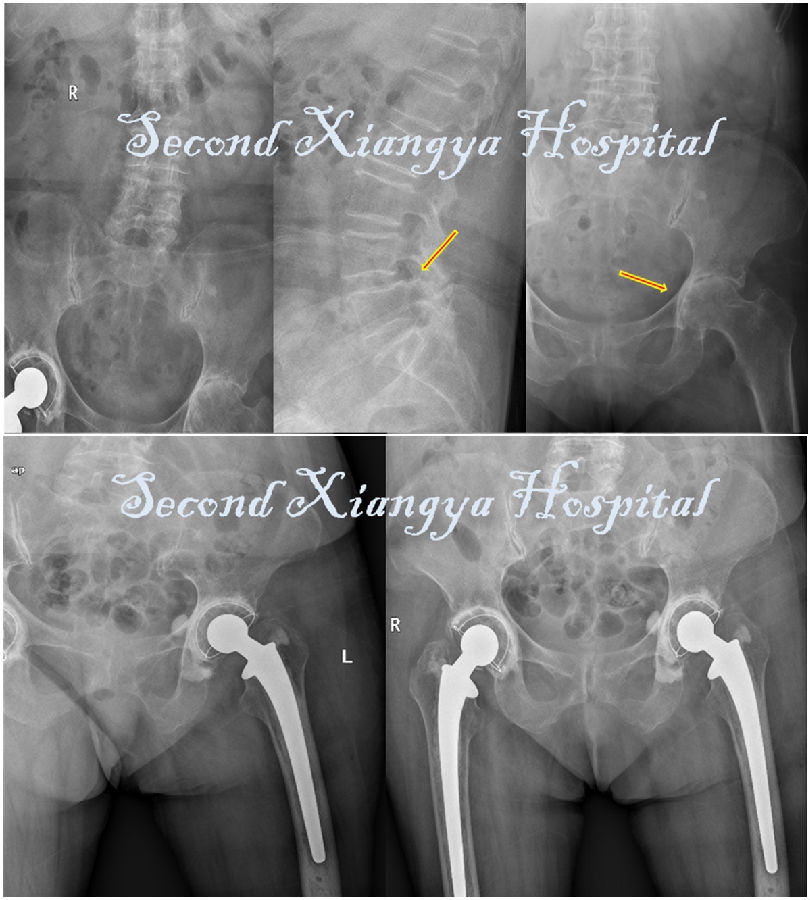

- 刘某某,女,63岁,脊柱后凸并腰痛20年

- 2年前加重并出现双侧臀部疼痛,沿双侧大腿外侧放射至膝关节,右侧为甚,并间歇性跛行及双下肢麻木感。

- 查体:脊柱S型侧弯,腰椎后凸,双下肢感觉减退,右髋关节活动明显受限,右侧直腿抬高及加强试验(+),双侧4字征(+),双侧托马斯征(+)。

- 腰椎退变性侧凸合并髋关节OA

- 手术:腰椎减压、长节段矫形融合术,2年后右侧THA,随后1年再行左侧THA,右髋随访2年松动进行翻修